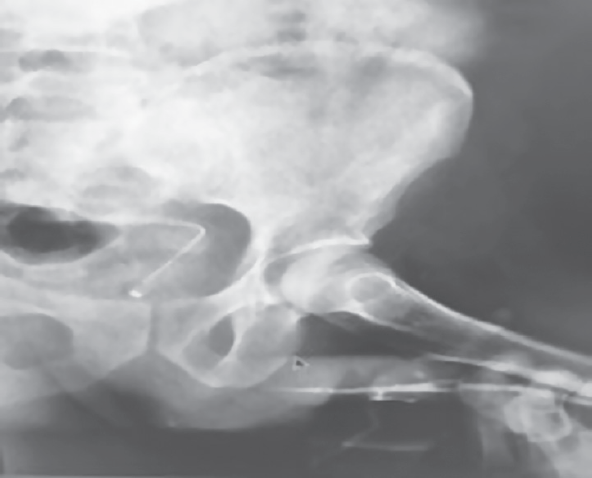

Под спинномозговой анестезией проведено экстренное оперативное вмешательство. После обработки операционного поля выполнено скальпирование полового члена до корня. В 3 см от головки пениса в месте перехода спонгиозного тела на правое и левое кавернозные тела выявлены дефект кавернозного тела размером до 2 см и разрыв уретры. Произведено сшивание уретры на катетере, ушиты дефекты белочной оболочки. Осуществлен контроль гемостаза. Затем — послойный шов на рану с иссечением крайней плоти и сшиванием внутреннего и наружного листов крайней плоти. Тугое бинтование полового члена. На 5-е сутки больной выписан по семейным обстоятельствам. Пациент повторно обратился за помощью через 2 недели после выписки с жалобами на наличие уретрального катетера и изменение цвета полового члена. Во время перевязки выявлено изменение цвета кожи полового члена (некроз кожи) (рис. 2). Под эндотрахеальным наркозом осуществлены некрэктомия, заместительная пластика кожи полового члена, троакарная цистостомия. Произведен забор донорской кожи с передней поверхности правого бедра (50 см3). Выполнена обработка раневой поверхности полового члена. На область кожного дефекта 3–4 см в диаметре уложен кожный графт, который фиксирован рассасывающейся нитью 5/0 викрил по всей его поверхности. Наложена асептическая повязка на половой член и место забора донорской кожи. Заживление раны удовлетворительное. В раннем послеоперационном периоде отмечено неадекватное функционирование цистостомы, что привело к подтеканию мочи по уретре из наружного отверстия мочеиспускательного канала и по его вентральной поверхности в средней трети полового члена (свищ уретры), возникла боль над лоном. Выполнить смену цистостомы не удалось, поэтому прибегли к открытой цистостомии. Обнаружен уретральный свищ в средней трети полового члена (рис. 3). От операции по поводу свища уретры пациент отказался. К моменту выписки проходимость мочеиспускательного канала была восстановлена (рис. 4). При пережатии цистостомы мочится самостоятельно, по данным урофлоуметрии максимальная скорость потока мочи составляет 19 мл/с.

Рис. 4. ретроградная уретрография после повторной операции

Fig. 4. Retrograde urethrography after repeated surgery